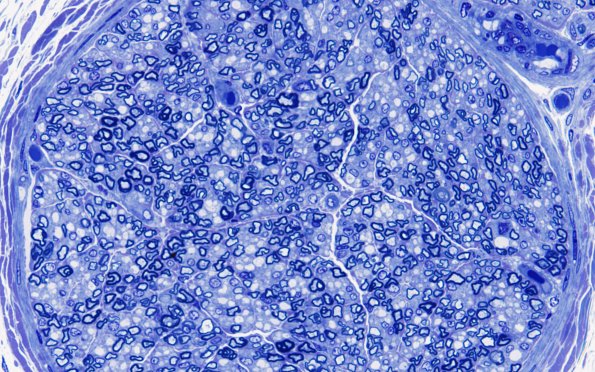

Washington University Experience | PERIPHERAL NEUROPATHY | 1 NORMAL NERVE ANATOMY | 6 Infant Peripheral Nerve | 3A3 Nerve, sural, infant, 4 wk (Case 3) 60XA

Higher magnification of one of the fascicles shown in #3A1. (Plastic section)